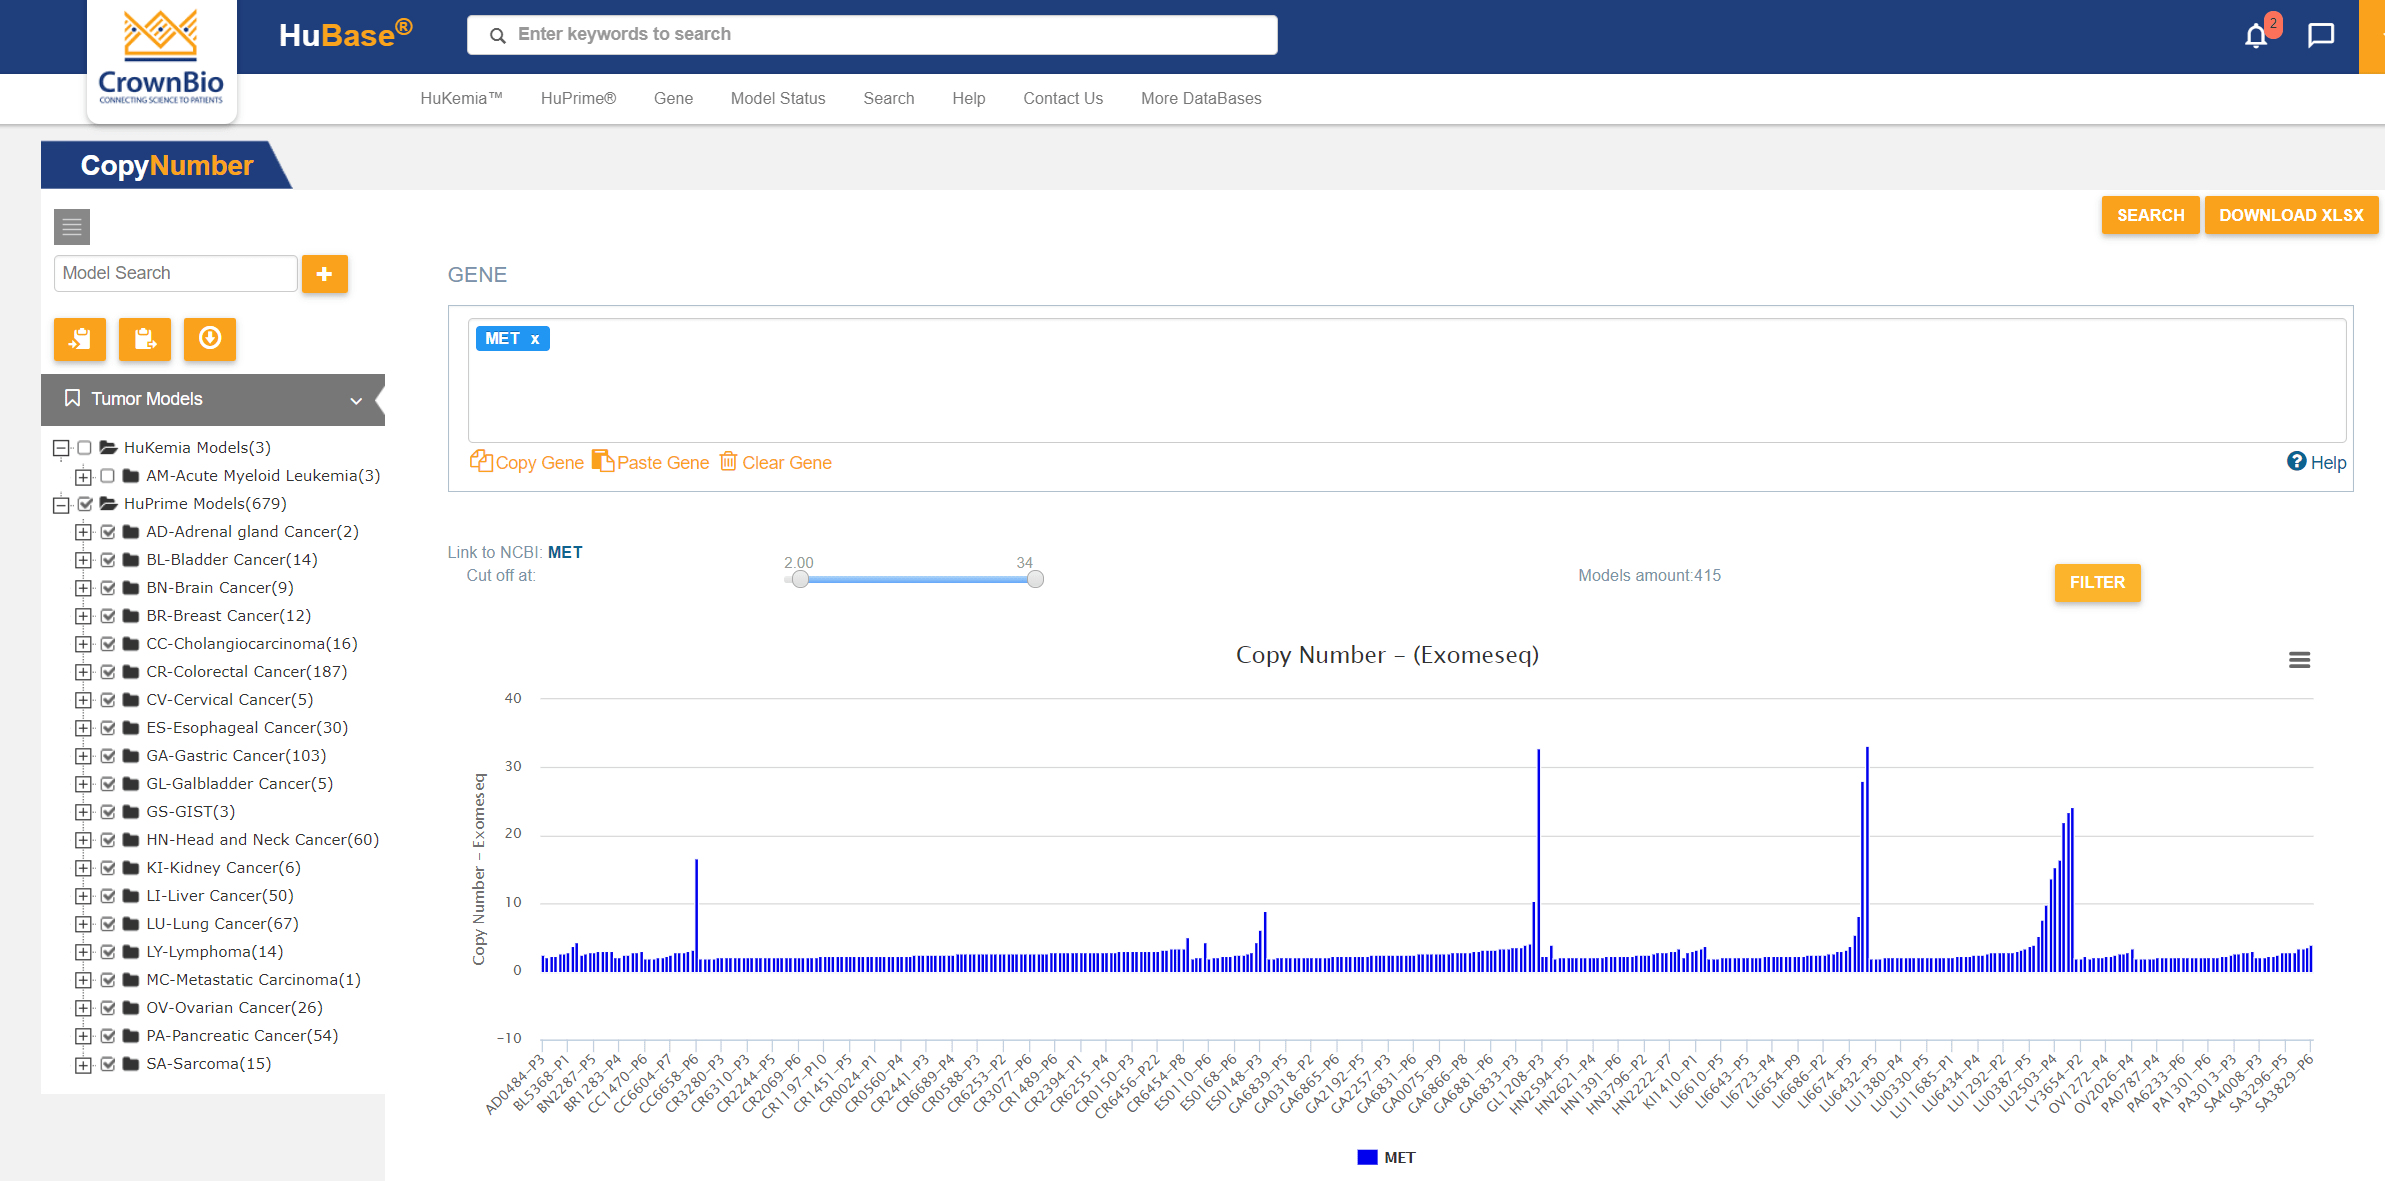

可搜索PDX模型数据库HuBase™中的大量特性鉴定数据包括:超过1,500个模型的RNAseq、超过680个模型的全外显子组测序、组织学、生长动力学以及SoC和研究性治疗数据。

具有典型白血病症状和最终死亡率的稳定模型,真实地代表了人类的情况。选择具有患者相关突变(例如: IDH2突变、FLT3-ITD(+)、BCR/ABL(+))的PDX模型来开发靶向制剂。探索大量模型特征:病理学、生长特性和对标准治疗实验制剂的反应。利用基因和基因组注释搜索符合您研究需求的模型。模型具备基因表达、基因拷贝数、突变和融合等特征。

搜索PDX基因组信息,例如:MET扩增用RNAseq基因表达数据和WES基因拷贝数数据。